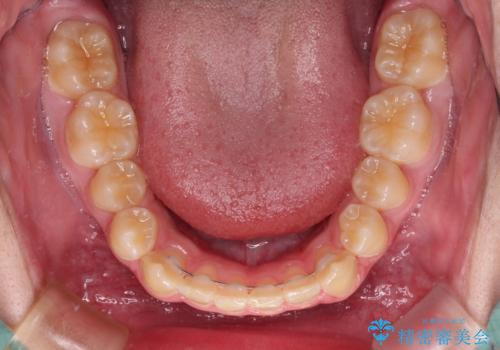

- 上下前歯のデコボコを気にして来院された患者様です。

「しっかりと装着する」が実行でき、高校3年生の秋には治療を終えることができました。